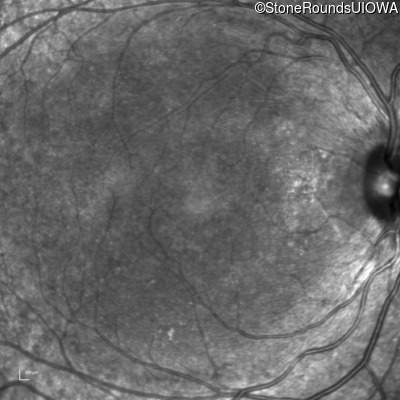

Blue Autofluorescence - Left - 20/20 -1

Exemplar